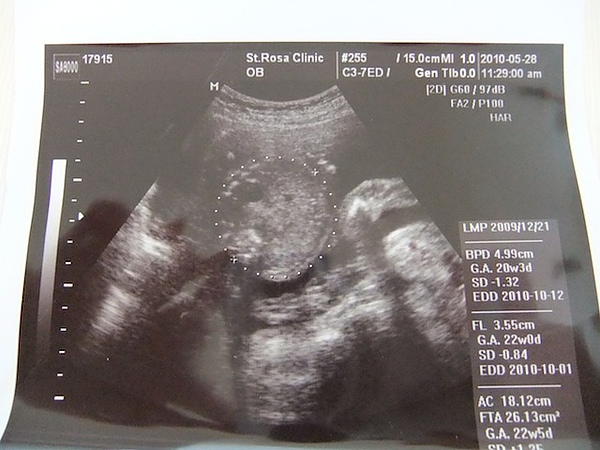

這次的產檢可能因為人很少,所以醫生很仔細的分別查看了虎寶的個別部位,這是虎寶目前在我肚子裡的樣子,頭上屁股下,後期時應該會轉下來吧?!還有心跳的頻率圖

這是虎寶圓滾滾的肚肚剖面圖

虎寶小小的腿,骨頭清晰明顯

虎寶的臉,醫生很可愛,還畫上圖案,怕我們看不懂!

在照超音波時,還看到虎寶在吸手指頭耶!好可愛喔~

,這次的產撿,除了還不知道虎寶的性別,讓我們有點失望以外,讓我比較失望的是~醫生說,虎寶只有488g,有點小,可是媽媽我卻已經胖到快6kg,也就是說,虎寶沒長多少,都胖到媽媽了!